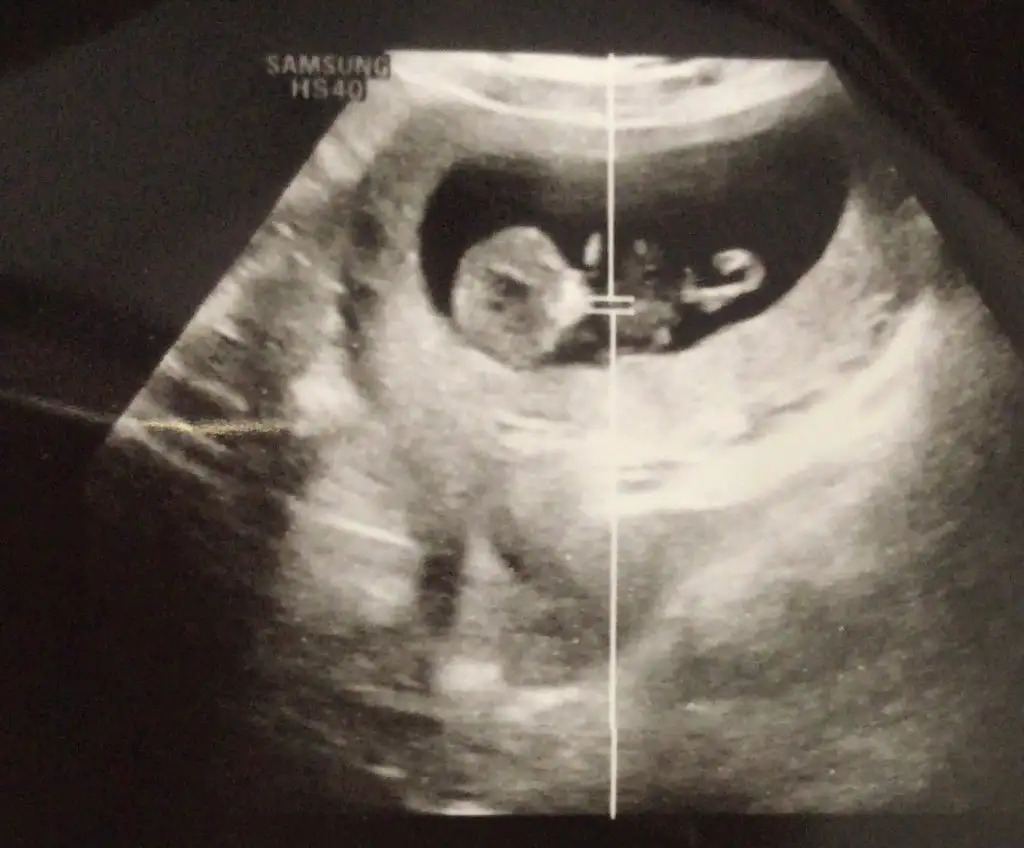

Kızlar doktorumdan geldim şimdi kılcal damarlarda pıhtılaşma mı ne olmuş o yüzden hafif lekelenme olmuş dedi progestan verdi eğer kanama çoğalırsa gene hemen gel bu sefer kan uyuşmazlığı iğnesini yapıcaz dedi yavrumu da gördüm

Kızlar doktorumdan geldim şimdi kılcal damarlarda pıhtılaşma mı ne olmuş o yüzden hafif lekelenme olmuş dedi progestan verdi eğer kanama çoğalırsa gene hemen gel bu sefer kan uyuşmazlığı iğnesini yapıcaz dedi yavrumu da gördüm Eki Görüntüle 3397680